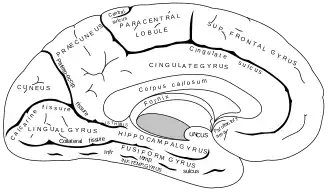

- Mediaal deel

De hippocampus en de amygdala zijn gelegen in het mediale (naar binnen gelegen) deel dat ook wel de mediotemporale cortex wordt genoemd. In het mediale deel van de temporale kwab liggen (van boven naar onder) twee windingen of gyri de gyrus parahippocampalis, door de sulcus rhinicus en de sulcus collateralis gescheiden van de gyrus fusiformis. De gyrus fusiformis wordt vervolgens weer begrensd door de sulcus occipitotemporalis.